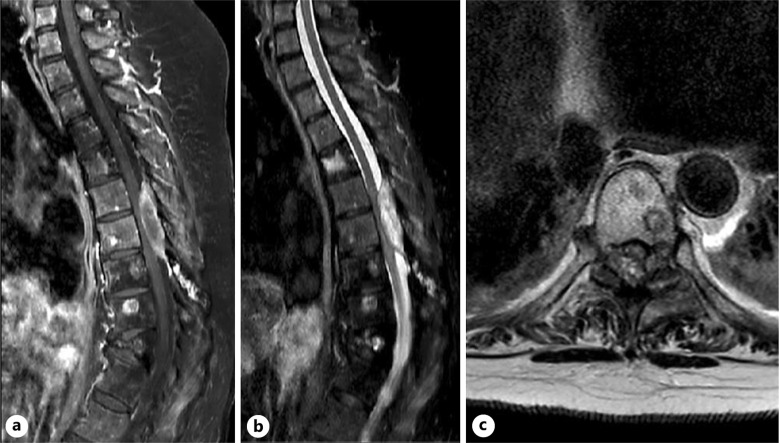

Case presentation: A 56-year-old female with presentation of acute on chronic mechanical low back pain was found to have multiple lytic lesions throughout the thoracolumbar spine arising from GIST metastases. Magnetic resonance imaging of the thoracic spine revealed a dorsal epidural enhancing mass spanning the T6-T8 levels with associated spinal cord compression and spinal cord signal change. The patient underwent urgent surgical decompression and resection of epidural tumor through T5-T8 decompressive laminectomy. Postoperatively, the patient initially did well with improvement in bilateral lower extremity sensation and bladder function. The patient passed away while at home due to undetermined causes 6 weeks postoperatively.